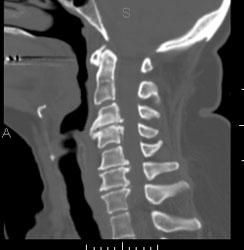

Een ct-scan van de wervelzuil wordt in princiepe aangevraagd om letsels

ter hoogte van de wervels te beoordelen, of om de doorgangkelijkhdeid

van het ruggemergkanaal te controleren. Den hier aan het opsporen

van een discus hernia, of een traumatisch letsel van eenwervel.

Vraagt in principe geen specifieke voorbereiding.

De patiënt gaat op de rug liggen op de onderzoekstafel en moet

blijven liggen tot na het onderzoek. Het is hier van belang dat de

patiënt niet meer van positie verandert.

Contrast wordt hier in sommige gevallen toegediend, maar dit is geen

regel.